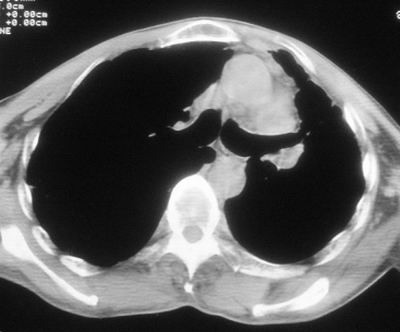

标题: CT11864:男,47岁,反复咳嗽、咯痰、咯血3年,请分析. [打印本页]

患者,男,47岁,反复咳嗽、咯痰、咯血3年,再发5天。痰培养未找到真菌、抗酸杆菌、癌细胞。

左肺上叶体积明显缩小,其内见多发透光区,纵隔向左侧移位,左肺下叶多发班片状病灶,边界模糊,1左肺上叶先天肺发育不全,2左肺下叶肺炎,

左肺上叶结核伴肺纤维化,纵隔移位,左肺下叶感染性病变,建议抗炎抗结核后复查,双肺气肿.

以下是引用xulianj在2008-2-25 21:01:00的发言:[br]左肺上叶结核伴肺纤维化有霉菌球形成,纵隔移位,左肺下叶感染性病变,建议抗炎抗结核后复查,双肺气肿.

考虑:左肺慢纤伴霉菌球形成、双肺全小叶型肺气肿。

1)考虑为:左肺上叶肺结核(空洞形成),伴左下肺感染;不排除霉菌感染可能。2)肺气肿。

左肺上叶结核伴肺纤维化空洞形成并左肺下叶感染,纵隔牵拉移位,建议作进一步检查排除左侧肺霉菌感染可能。